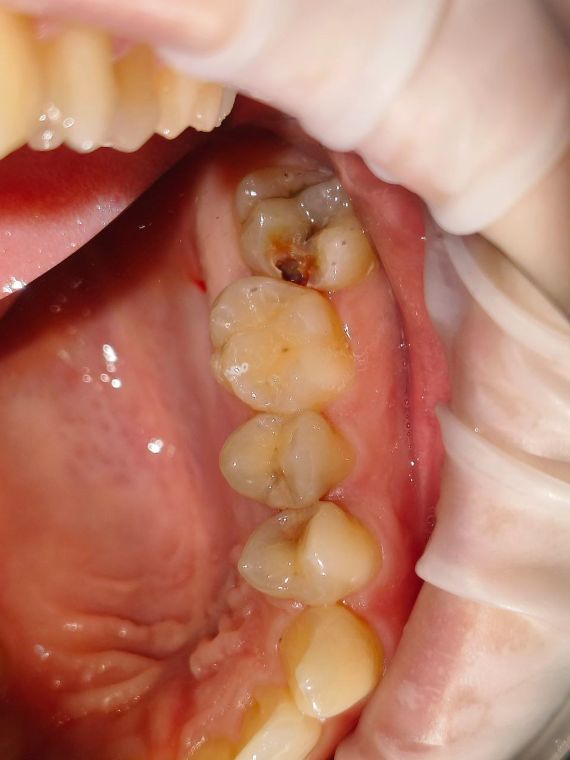

как выглядит зубной кариес на жевательном зубе

На фото представлен глубокий кариес на жевательном зубе

зуб до лечения

Глубокий кариес на жевательной поверхности легко определяется врачом при осмотре, зуб изменен в цвете с светло желтого на сероватый, можно обнаружить полости темного цвета в которых застревает стоматологический зонд.